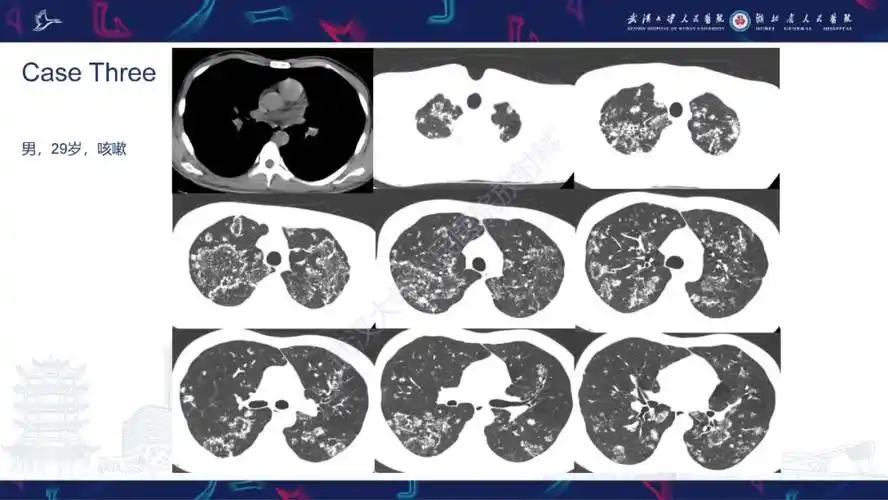

活动性肺结核不典型ct表现